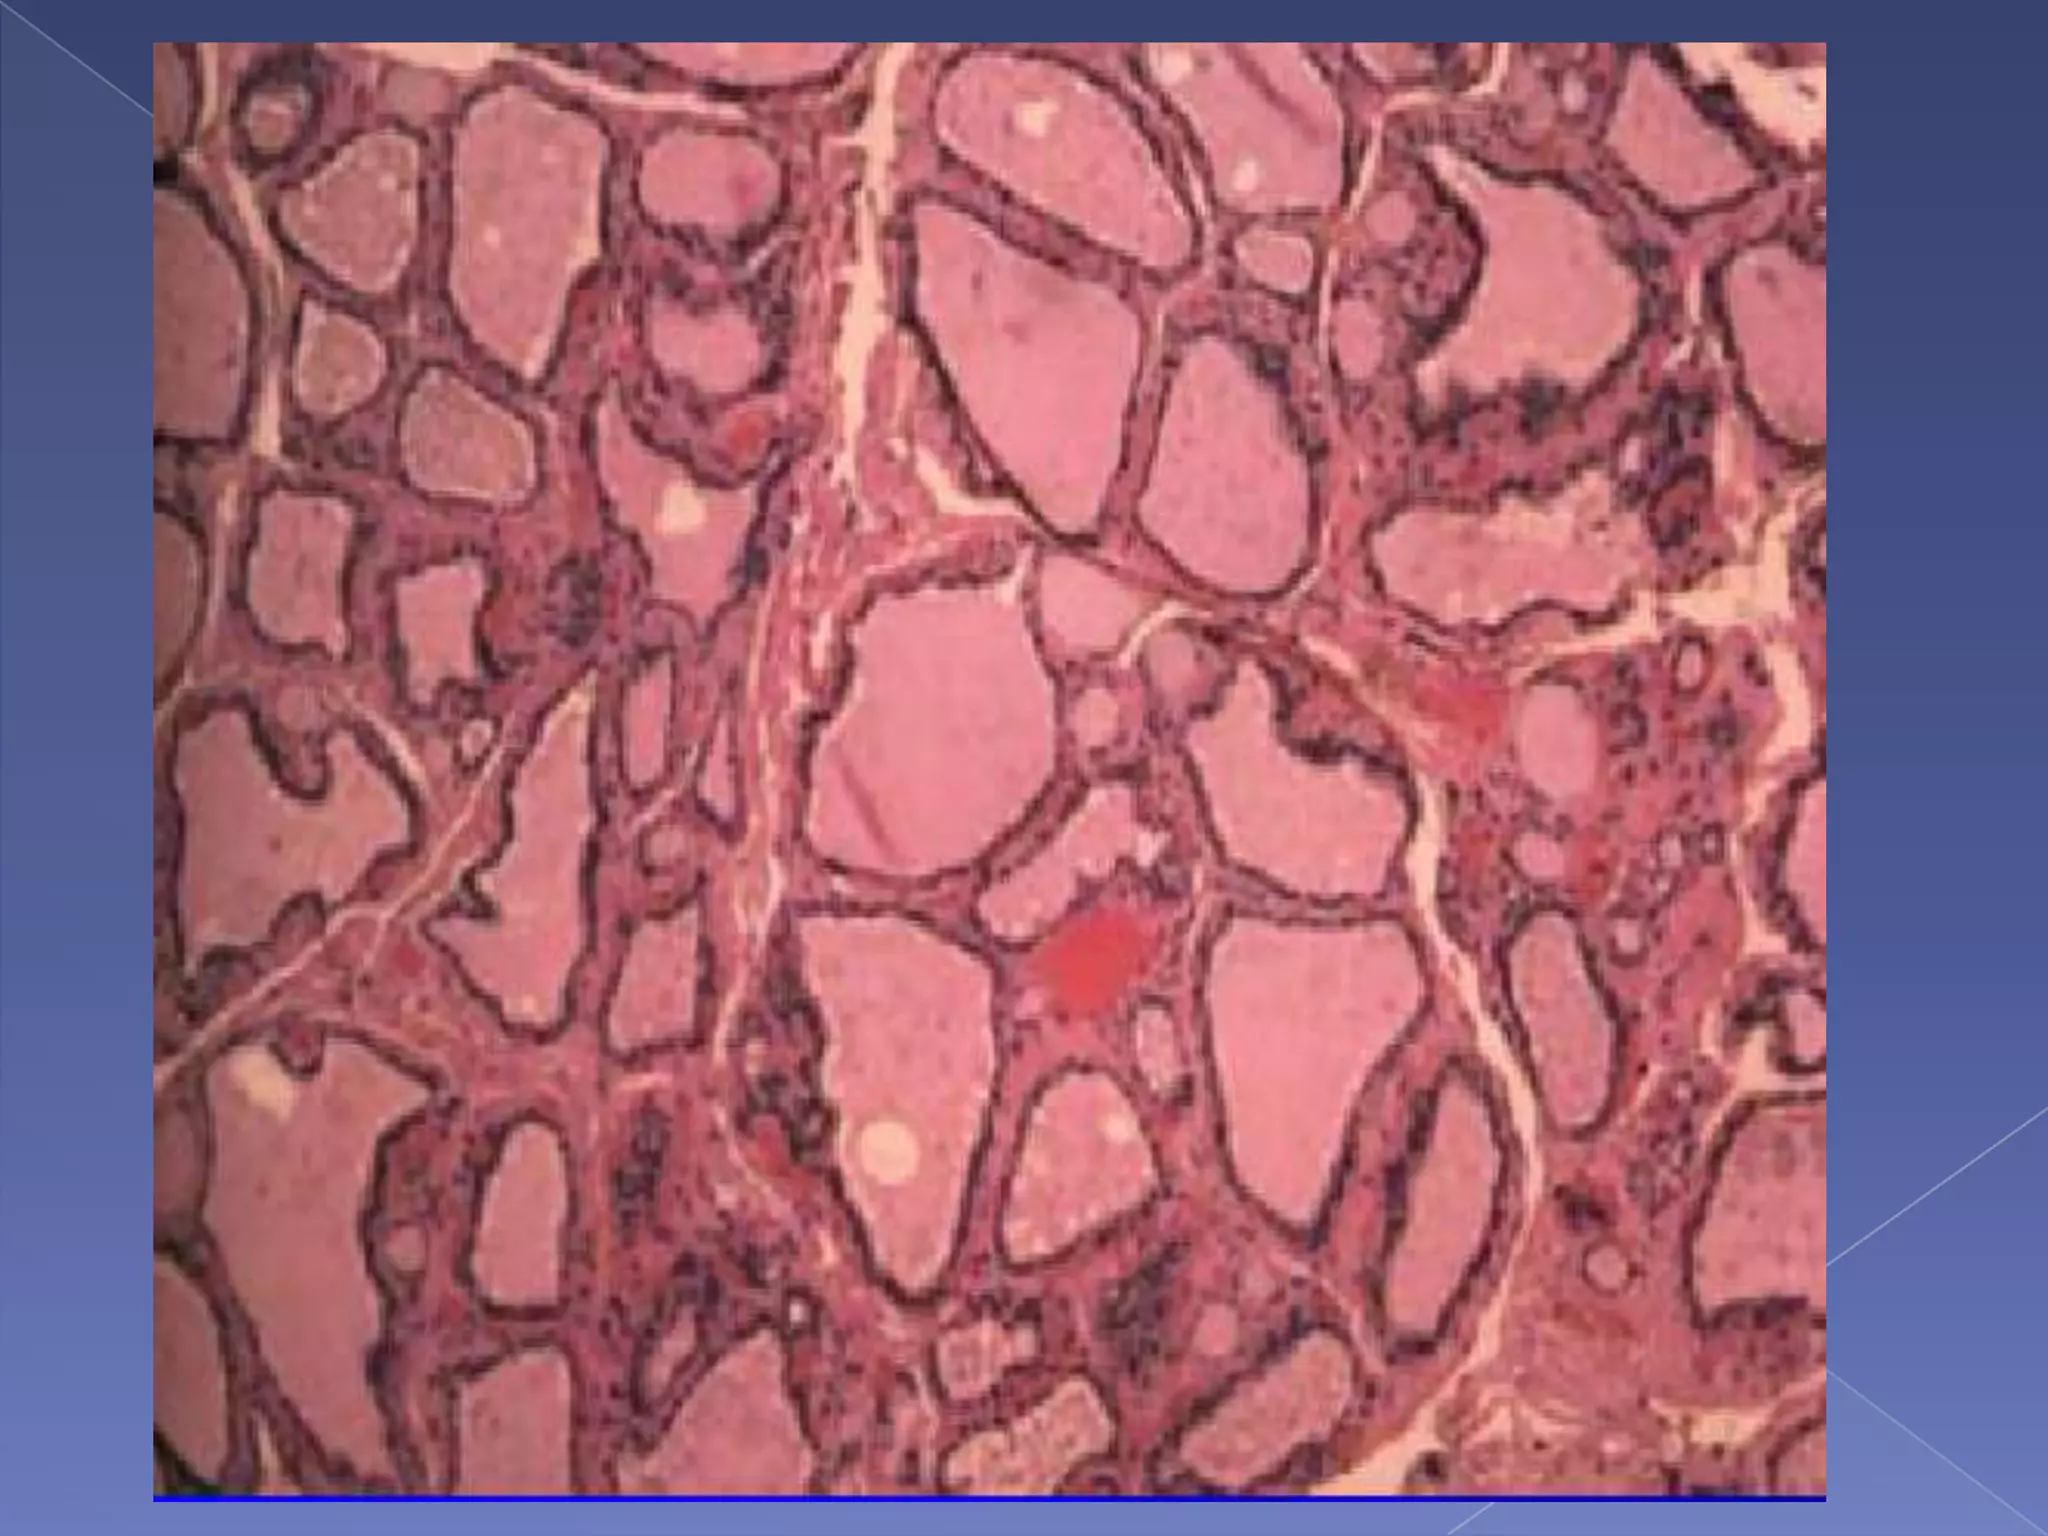

RRLN runs diagonal with the TEGHistology of thyroid glandLobule:  20-30 folliclesFollicle:functional unit

Follicular cells

Contains colloidParafollicular cell or C-cell

RRLN runs diagonalwith the TEGHistology of thyroid glandLobule: 20-30 folliclesFollicle:functional unit

• 19.